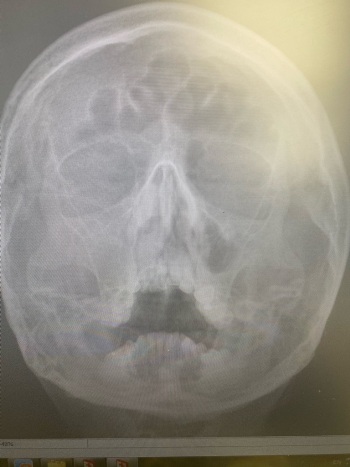

Полипозный синусит

В клинику №1 ВиТерра Беляево к врачу - отоларингологу обратился пациент с жалобой на затруднённое носовое дыхание.

При риноскопии визуализировалась обтурация правой половины носа полипозными разрастаниями.

Пациент был направлен на рентгеновское обследование.

По рентгену: тотальное заполнение правой в/ч пазухи полипозными разрастаниями + прорастание в средний носовой ход.

Диагноз: Полипозный синусит.

Пациенту была назначена консервативная терапия с дальнейшей эндоскопической операцией.